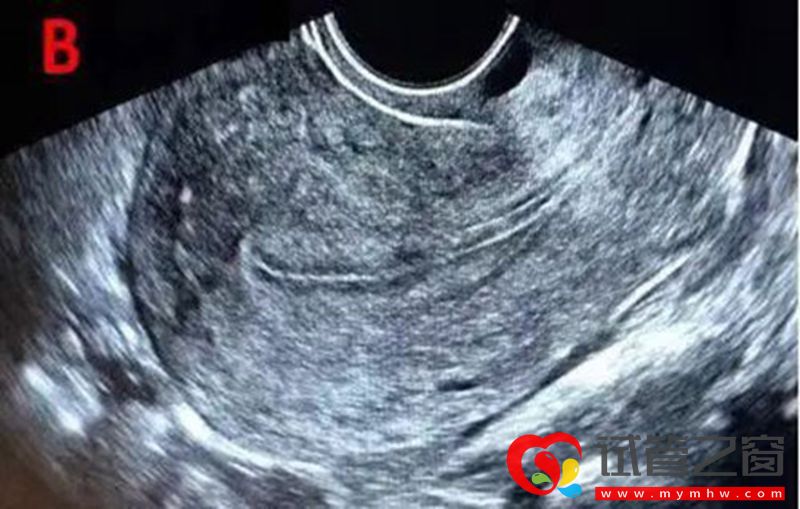

B型为弱三线型,为均一的中等强回声,宫腔中线回声不明显,一般见于黄体早期。

C型为均质强回声,为均质强回声,无宫腔中线回声,一般见于黄体晚期。